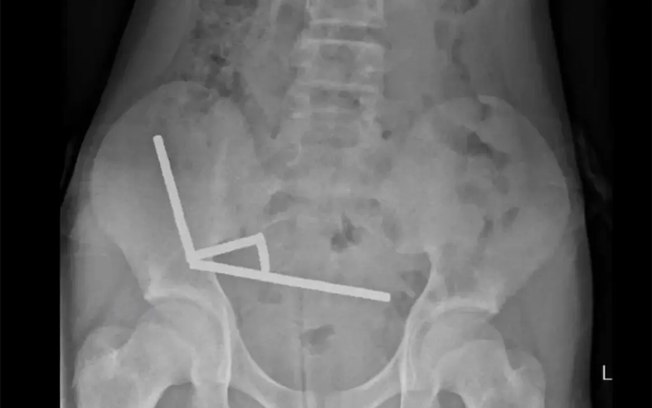

Exames de raio-X mostraram quatro fileiras de ímãs presos em diferentes partes do intestino, que se atraíam entre si e comprimiam o tecido intestinal, cortando o fluxo de sangue. Essa pressão provocou várias áreas de necrose, ou seja, morte do revestimento intestinal, o que exigiu uma cirurgia de emergência para a retirada dos ímãs e das partes afetadas do intestino.

Segundo o relatório médico, os ímãs mediam cerca de 5 por 2 milímetros e se alinharam em quatro correntes dentro do intestino. A força magnética fez com que partes do órgão se grudassem, comprimindo o tecido entre elas. Os cirurgiões alertaram que pacientes submetidos a esse tipo de procedimento podem desenvolver complicações duradouras, como obstruções intestinais, hérnias e dores abdominais crônicas.